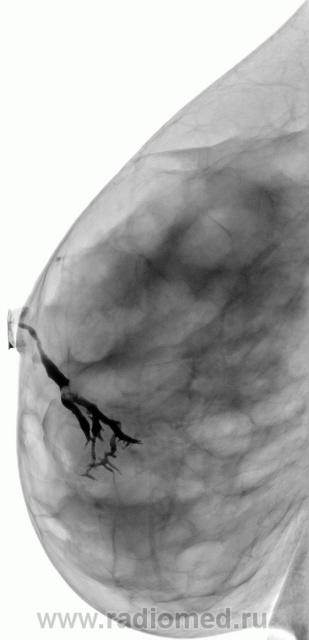

Случай 2.  Внутрипротоковое образование.   Случай Рыбаковой Л.А.

Пациентка предъявляет жалобы на наличие кровянистых выделений из протоко правой молочной железы в течение года. Проведено УЗИ, патологии не выявлено. Взяты мазки- отпечатки. Пациентка направлена "на дуктографию". Бужирован проток, с трудом введено 0,7 мл. контрастного вещества. Контрастирован проток в нижне-внутреннем квадранте правой молочной железы. Центральный проток равномерно расширен, определяется внутрипротоковое образование, контуры его ровные, чёткие. Данное образование практически обтурирует просвет протока.